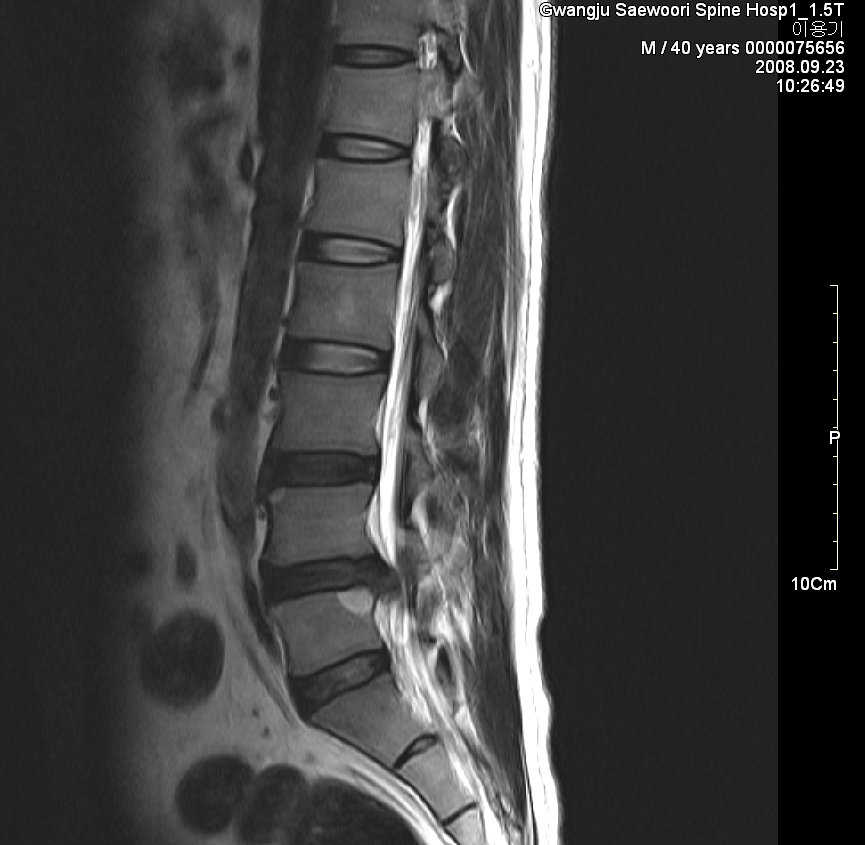

그림. sequestration사진. 월산동 남편 mri

그림. 흡수된 사진

symptom : local low back pain, lt buttock pain, lt leg radiating pain 허리에서 엉덩이 종아리까지 쑤시고 애림. 야간에는 통증으로 잠을 못 이룸.

sign : l5 sensory impairment, motor nerve intact(manual muscle powr test - nonspecific), dtr(++/++)

evidence : l-spine mri 사진

치료과정

침상안정 3일, 3일동안 허리 얼음찜질 1시간 30분씩 하루 5회 시행,

제가 2년 전 월산원광한방병원에서 치료한 환자 사진입니다. 수술을 위주로 치료하는 의사가 판단하기에 황당하게 보일지 모르겠습니다. 하지만 이 환자는 현재 가끔 골프도 치면서 허리디스크를 앓기 전보다 더 건강한 허리를 가지고 살아가고 있습니다.